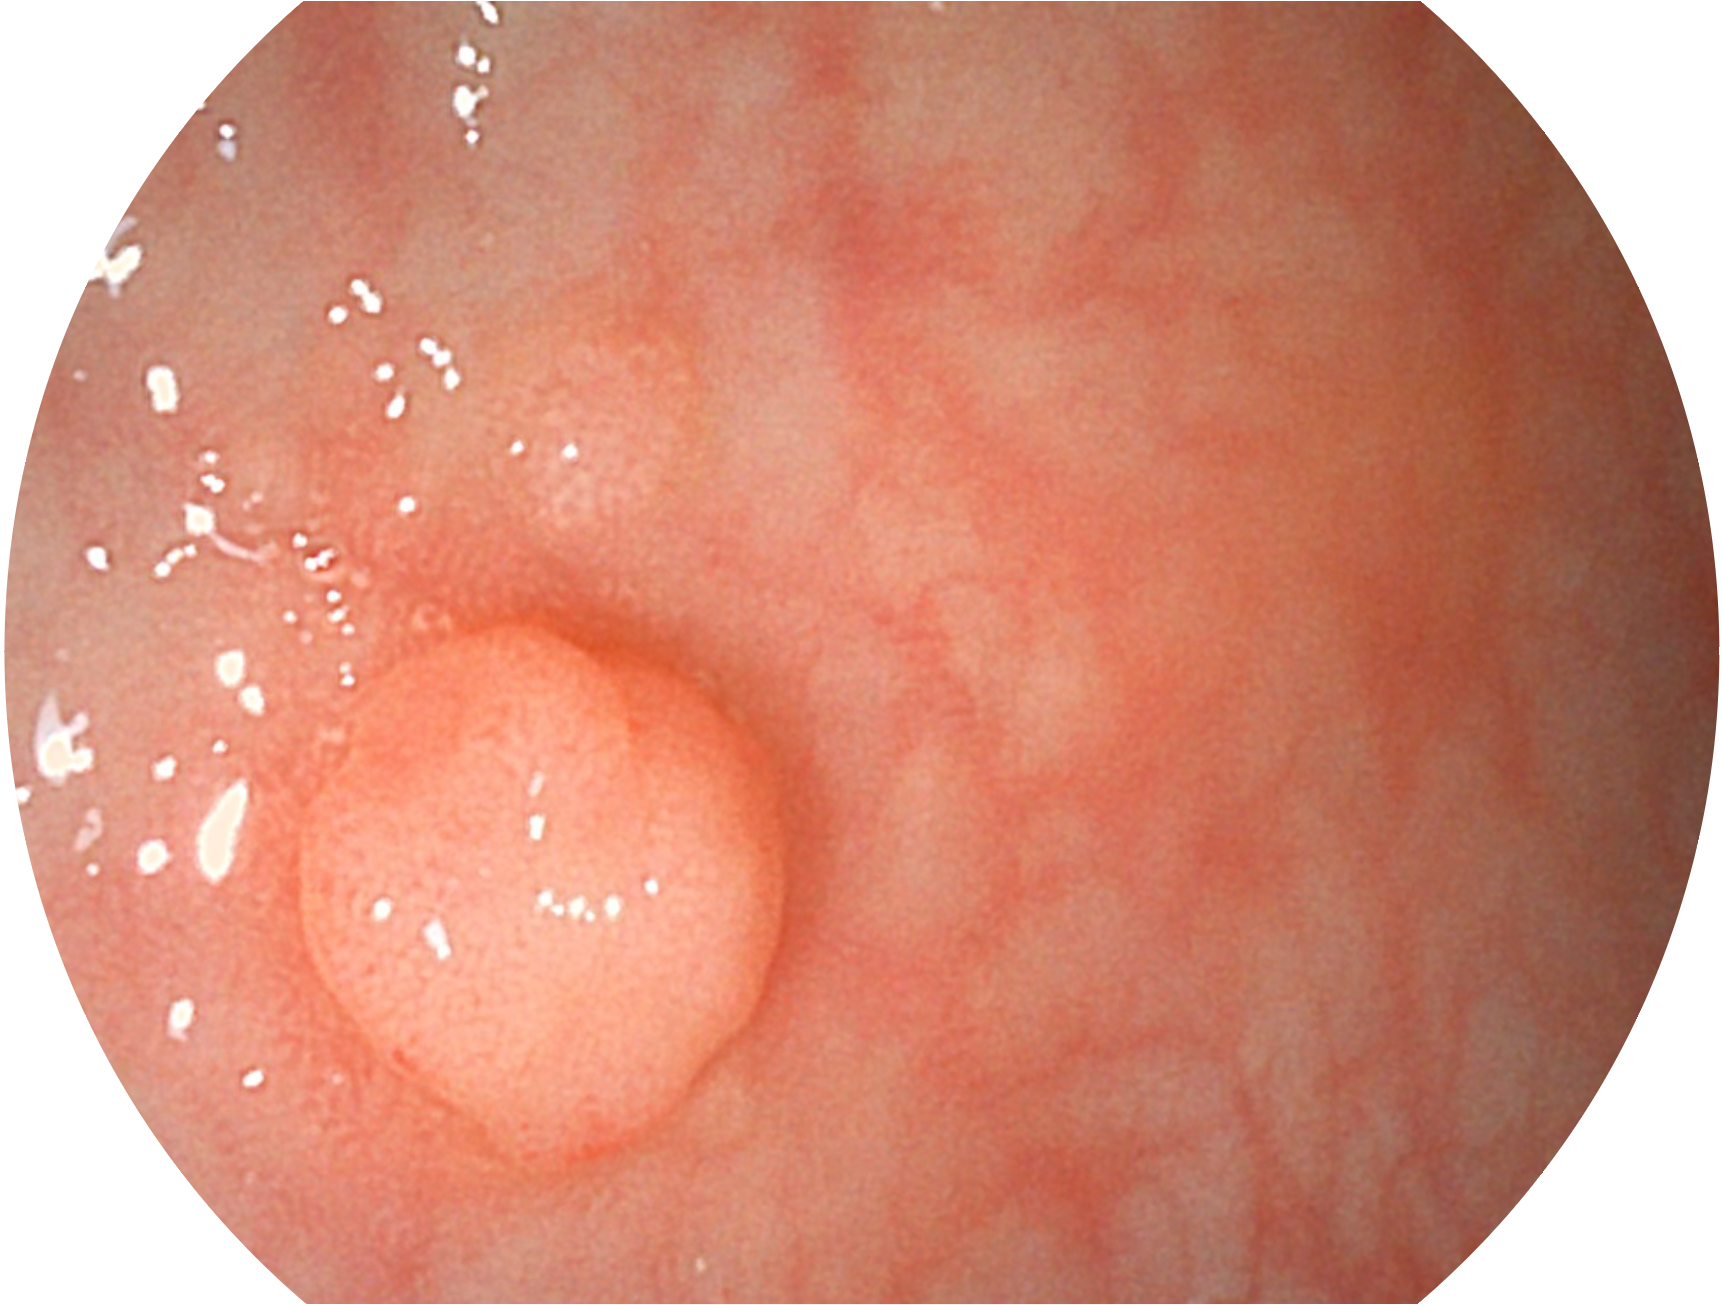

milan米兰新开发的内镜染色技术,主要是基于多波长LED 光源的开发,VLS-55Q 四波长LED 光源是由四个不同颜色的LED光按照相应照明模式所规定的特定发光比例进行合束后形成,合束后形成的照明光的光谱由红光、绿光、蓝光及蓝紫光这四个不同的波段范围构成。具有更高光谱自由度,通过光谱比例的控制,实现了聚谱成像技术,英文全称为“Spectral Focused Imaging, SFI”,缩写为“SFI”和光电复合染色成像技术,英文全称为“Versatile Intelligent Staining Technology, VIST”,缩写为“VIST”。